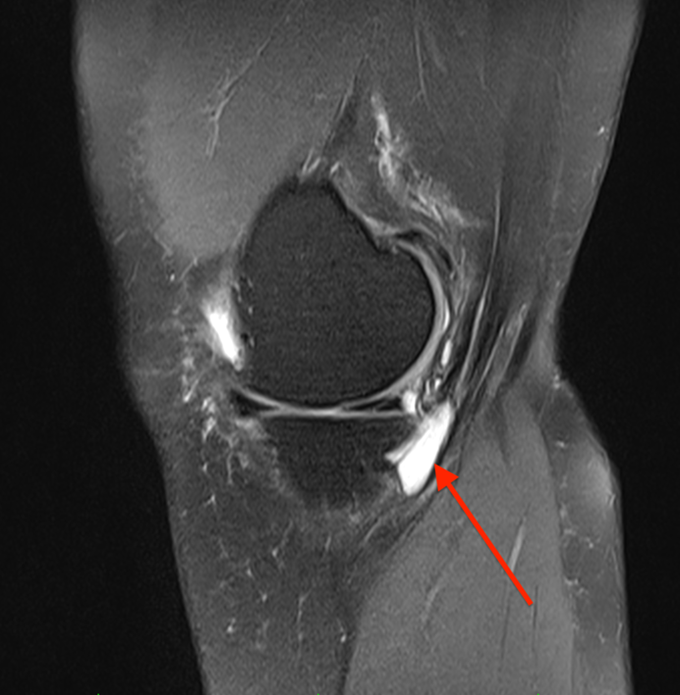

MRI jest złotym standardem w różnicowaniu zespołu zapalenie gęsiej stopki od innych wewnątrzstawowych i pozastawowych patologii kolana6. Charakterystyczne cechy obrazu MRI to:

- Płyn w kaletce pes anserinus – hipointensywny w T1, hiperintensywny w T2 Zdjęcie 2.

- Zlokalizowany poniżej ścięgien pes anserinus, na wysokości górnego końca kości piszczelowej

- Często współistnienie zmian zwyrodnieniowych w stawie kolanowym

- Możliwość wykrycia obrzęku tkanek miękkich i szpiku kostnego

Należy pamiętać, że obecność płynu w kaletce u 5% osób bezobjawowych oznacza, że rozpoznanie zespołu zapalenie ścięgien gęsiej nie może opierać się wyłącznie na obrazie MRI – konieczna jest korelacja z objawami klinicznymi 3,6.

Zdjęcie 2. Obrazy rezonansu magnetycznego, czerwona strzałka wskazuje obecność płynu wokół ścięgien, co sugeruje zapalenie.